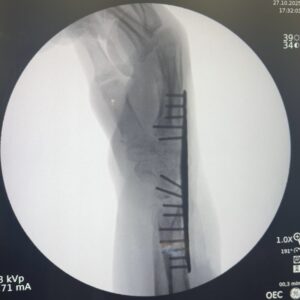

Na artrodese total do punho, as 5 articulações geralmente necessárias para o sucesso da fusão são:

Aradiosemilunar, radioescafoide, semilunocapitato, piramidalhamato e 3 CMC

Bradioescafoide, escafotrapezoide, radiosemilunar, semilunocapitato e 3 CMC

Cradiosemilunar, radioescafoie, escafocapitato, semilunocapitato e 3 CMC

Dradioescafoide, radiosemilunar, radiopiramidal, semilunocapitato e 3 CMC